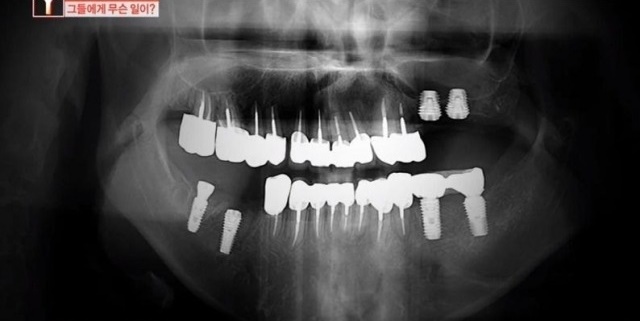

그는 치아에 생긴 얼룩만 지우고 싶었는데 치과의 원장은 윗니에 충치가 조금씩 있다며 잇몸마취 상태로 윗니 10개를 마음대로 갈아버렸다고 한다.

피해자의 치아 상태를 살펴본 다른 치과 전문의는 “충치가 확실하지 않고 충치가 없었다고 보이는데 (윗니를) 많이 갈아버린 것”이라며 “(의사가 한) 행위 자체로만 보면 상해다”라고 목소리를 높였다.

과잉진료 의혹을 받고 있는 왕지혜(가명) 원장은 “피해자분들께서는 단순히 치아 하나 치료하러 갔는데 동의도 안 받은 상태에서 8~10개 발치를 해서 피해를 많이 봤다고 얘기하더라”고 하자, 왕원장은 “치과 진료는 환자가 의식이 있는 상태에서 이뤄지는 치료다.

제작진이 해당 사건을 파악해보니 피해자들은 약 450여 명 정도로 밝혀졌는데 문제의 치과는 폐업을 했다.